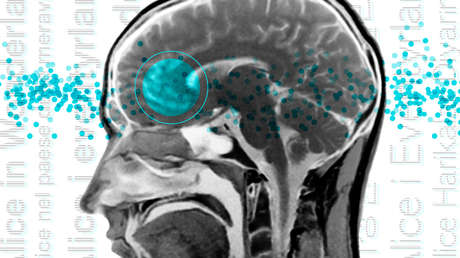

La molécula clave se denomina CGRP y permite que las neuronas en dos áreas separadas del cerebro agrupen señales sensoriales amenazantes en una sola señal unificada, la etiqueten como 'negativa' y la transmitan a la amígdala, que se encarga de traducirla en miedo.

La inmensa mayoría de amenazas externas implican señales multisensoriales. En un incendio, por ejemplo, una persona es capaz de oler el humo, sentir el calor y ver las llamas, y todo ello trabajando junto pone en marcha el engranaje del miedo.